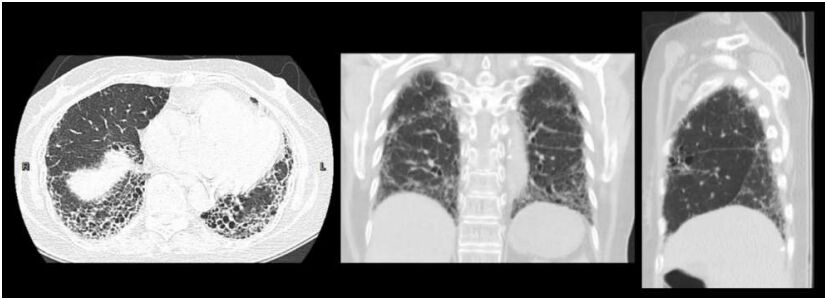

8. 63歲男性,因為鬱血性心臟衰竭住院,BMI 42 kg/m², 入院時氧氣濃度(SaO2)為75% , 血壓為140/80 mmHg。胸部X光顯示肺水腫,心跳數為136/min,同時合併出現非持續性心室頻脈(non-sustained ventricular tachycardia)。心臟超音波顯示兩心室(左右心室)功能皆不全,左心室射出分率為15%, 實驗室檢查顯示,腎功能: creatinine clearance 80 ml/min, NTproBNP 3000 pg/ml, 右心導管顯示低心輸出率 (cardiac index of 1.5 l/min/m²),肺動脈楔壓(PCWP)為20 mmHg。下列心衰竭藥物的注射選擇何者最為恰當? (A) Dobutamine 1~2 ug/kg/min 靜脈注射。 (B) Dopamine 10 ug/kg/min 靜脈注射。 (C) Norepinephrine 3ug/kg/min 靜脈注射。 (D) Levosimendan 0.10 ug/kg/min 靜脈注射。 (E) Dopamine 2 ug/kg/min 靜脈注射。